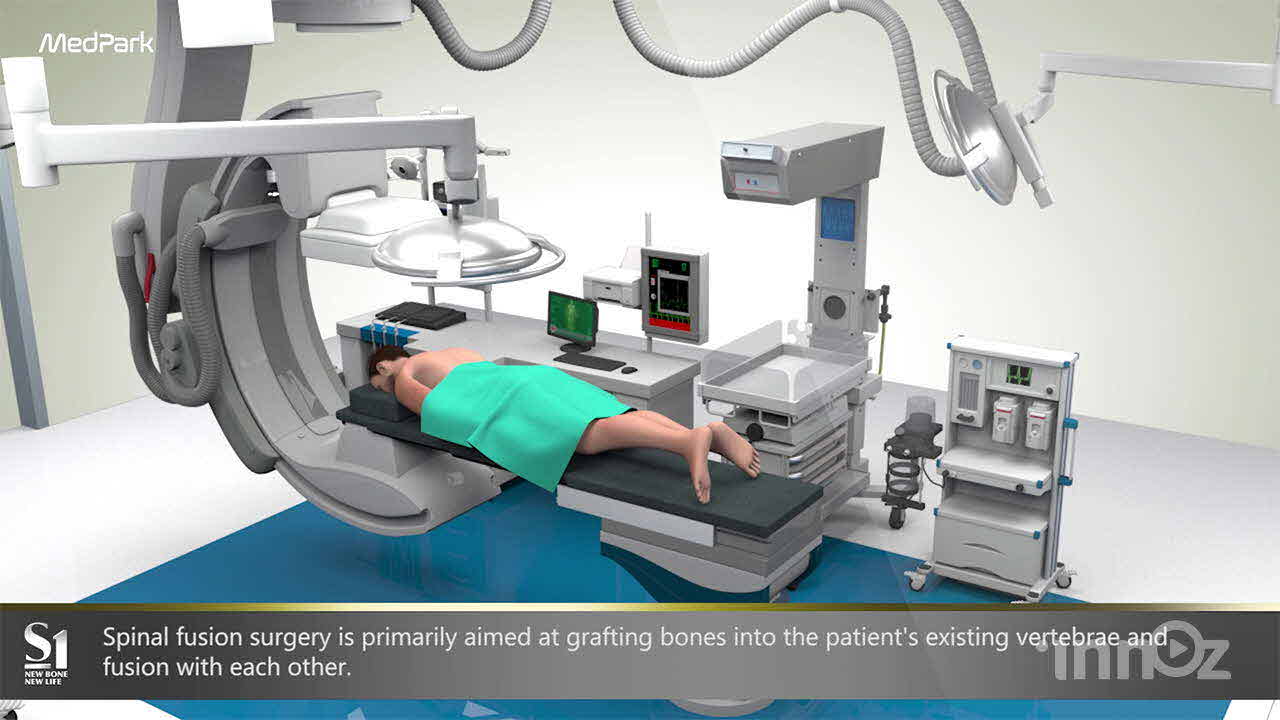

의료, 건설, 산업, VR AR, AI 등 고퀄리티 3D영상제작

이노즈는 AI영상제작, 3D영상 제작 전문기업으로, 다양한 산업 분야에 걸쳐 혁신적이고 몰입감 있는 3D 콘텐츠를 제공합니다. 제품 홍보, 건설 시뮬레이션, 애니메이션 등 맞춤형 영상으로 고객사의 가치를 시각적으로 효과적으로 전달합니다. 고품질의 3D 시각화와 창의적인 연출을 바탕으로, 고객의 목표를 실현하는 독창적이고 강력한 시각적 경험을 제공합니다. 이노즈의 포트폴리오는 고객의 아이디어를 현실로 구현한 다양한 성공적인 프로젝트로 가득합니다.

메드파크